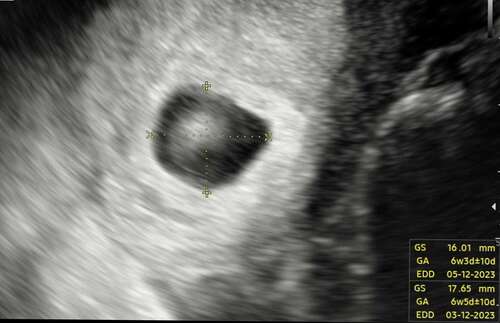

Geen ovulatietesten gedaan maar wel ongeveer gevoeld, dus niet zeker maar 3 ...

Tenzij je een hele late eisprong en innesteling hebt gehad.

In mijn ogen is dit een mooie vooruitgang. Oké je bent minder ver maar je b ...

Ja is ook zo! Maar het maakt me onzeker omdat ik vrij vaak vaste cyclus heb in de maand.

Nu was ik 1 dag erg ziek en koorts en moe. En die dag was ik erg licht bijna niet zichtbaar de test en dat was 2 dagen voor nod gebaseerd op cyclus dagen 28